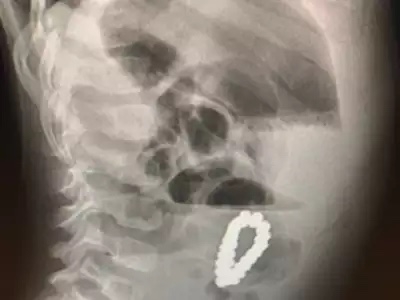

ويعتقد الأطباء أن الصبي ابتلع كل حبة على حدة، وبسبب خصائصها المغناطيسية علقت الخرزات معًا في الداخل على شكل سوار، وقد سد الخرز المغناطيسي أمعاء الطفل وحفر ثقوبًا، وتم تشخيص انسداد الأمعاء نتيجة تناول الخرز، وخضع الطفل لإجراء عملية جراحية لاستخراج 18 حبة سداسية وإصلاح الثقوب التي لحقت بأمعائه، ثم خرج من المستشفى بعد ستة أيام، وظل تحت الملاحظة والفحص لمدة ستة أشهر، حتى تماثل الشفاء وتعافى بشكل جيد.